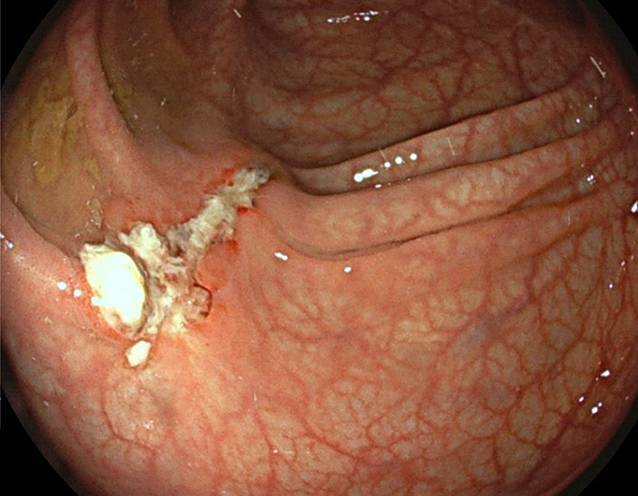

Nach stationärer Aufnahme zur weiteren Abklärung wurde eine Kontrastmittel-CT des Abdomens durchgeführt, welche die Hydronephrose Grad III links auf eine Obstruktion durch den Endoskopieclip zurückführte (Abb. 1). In einer Akutkolonoskopie wurde der Mainz-Pouch II als normal befundet, jedoch konnten die Ureterenmündungen beidseits – bis dato in den jährlichen Nachsorgekolonoskopien im intramuralen Bereich unauffällig – nicht dargestellt werden. Es zeigten sich lediglich zwei fibrinbedeckte Polypenabtragungsstellen (Abb. 2). In Zusammenschau der Befunde waren die Ureterenmündungen im Pouch als vermeintliche Polypen abgetragen, verödet und geclippt worden. Der in der CT beschriebene Clip war zwischenzeitlich offenbar abgegangen.